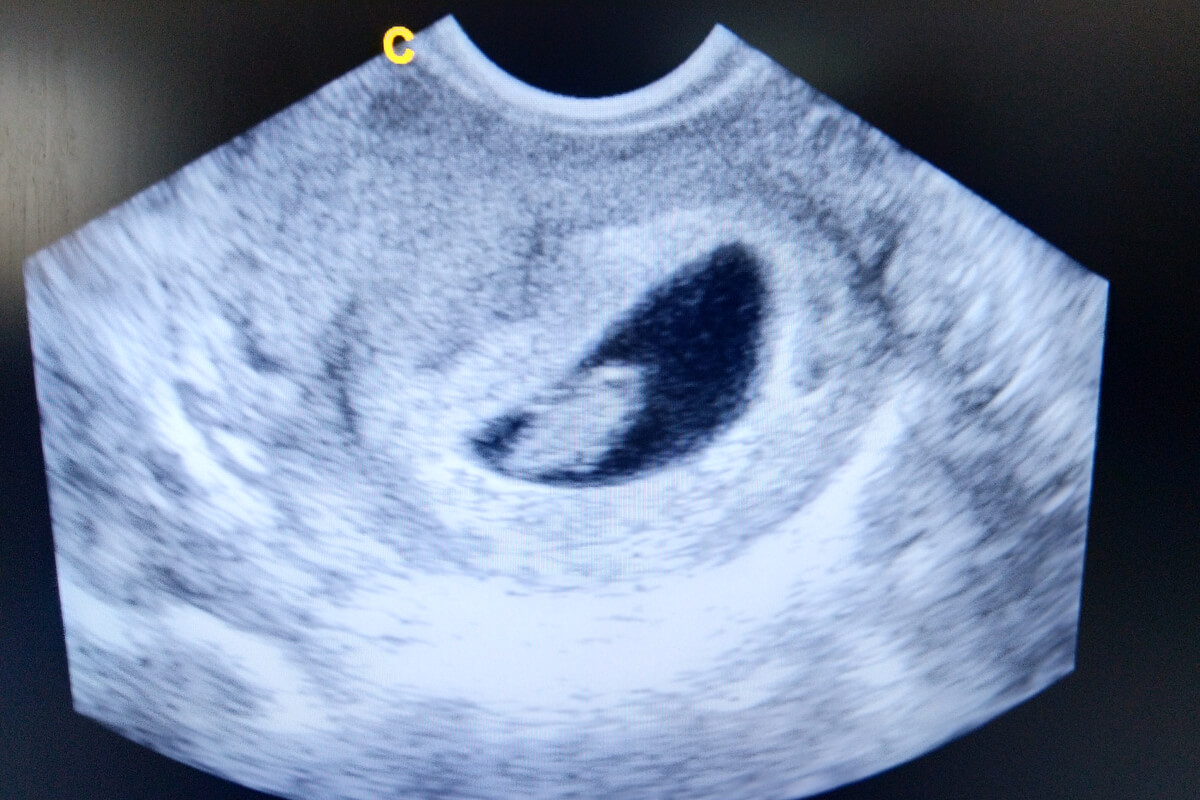

Este será el aspecto que tendrá tu bebé en una ecografía durante las semanas 6 y 7 del embarazo:

Su pequeño corazoncito late con la fuerza suficiente para ser observable con un ecosonograma intravaginal, así que si te realizas este examen durante esta semana podrás escuchar los latidos del corazón de tu bebé. Este será un momento que quedará guardado para siempre.